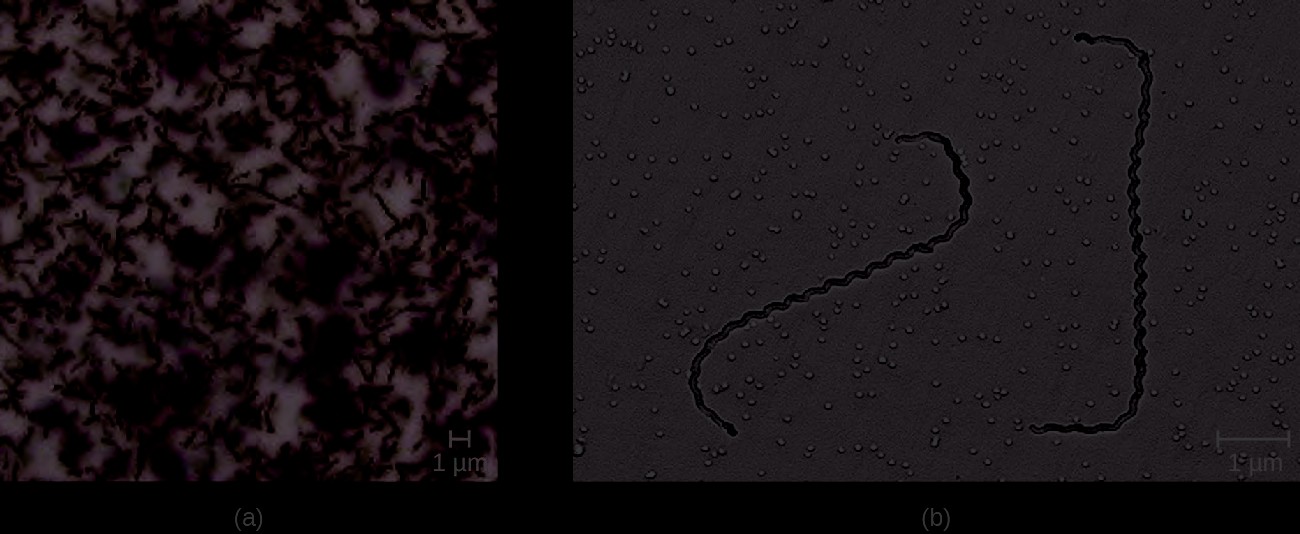

Diagnosis of vaginal candidiasis can be made using microscopic evaluation of vaginal secretions to determine whether there is an excess of Candida. Culturing approaches are less useful because Candida is part of the normal microbiota and will regularly appear. It is also easy to contaminate samples with Candida because it is so common, so care must be taken to handle clinical material appropriately. Samples can be refrigerated if there is a delay in handling. Candida is a dimorphic fungus, so it does not only exist in a yeast form; cultivation can be used to identify chlamydospores and pseudohyphae, which develop from germ tubes (Figure 23.22). The presence of the germ tube can be used in a diagnostic test in which cultured yeast cells are combined with rabbit serum and observed after a few hours for the presence of germ tubes. Molecular tests are also available if needed. The Affirm VPII Microbial Identification Test, for instance, tests simultaneously for the vaginal microbes C. albicans, G. vaginalis (see Bacterial Infections of the Urinary System), and Trichomonas vaginalis (see Protozoan Infections of the Urogenital System).

Figure 23.22 Candida can produce germ tubes, like the one in this micrograph, that develop into hyphae. (credit: modification of work by American Society for Microbiology)